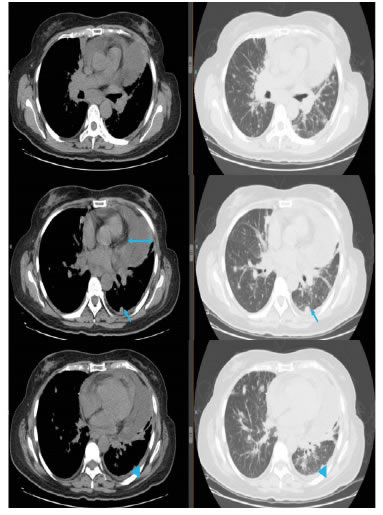

Después de la quimioterapia, en la tomografía por emisión de positrones (PET-CT) se observaron los implantes pleurales, con engrosamiento pleural y pericárdico, y derrame pericárdico. Hubo progresión según los criterios de reacción por PET-CT (Positron Emission Tomography Response Criteria, PERCIST). No se observaron signos de taponamiento cardiaco (figura 6).

Figura 6.

PEC-CT, ventanas mediastinal y pulmonar: derrame

pericárdico. La doble flecha muestra una separación de 2 cm del

pericardio, la flecha señala los implantes pleurales y, la cabeza de

flecha, el engrosamiento pleural.